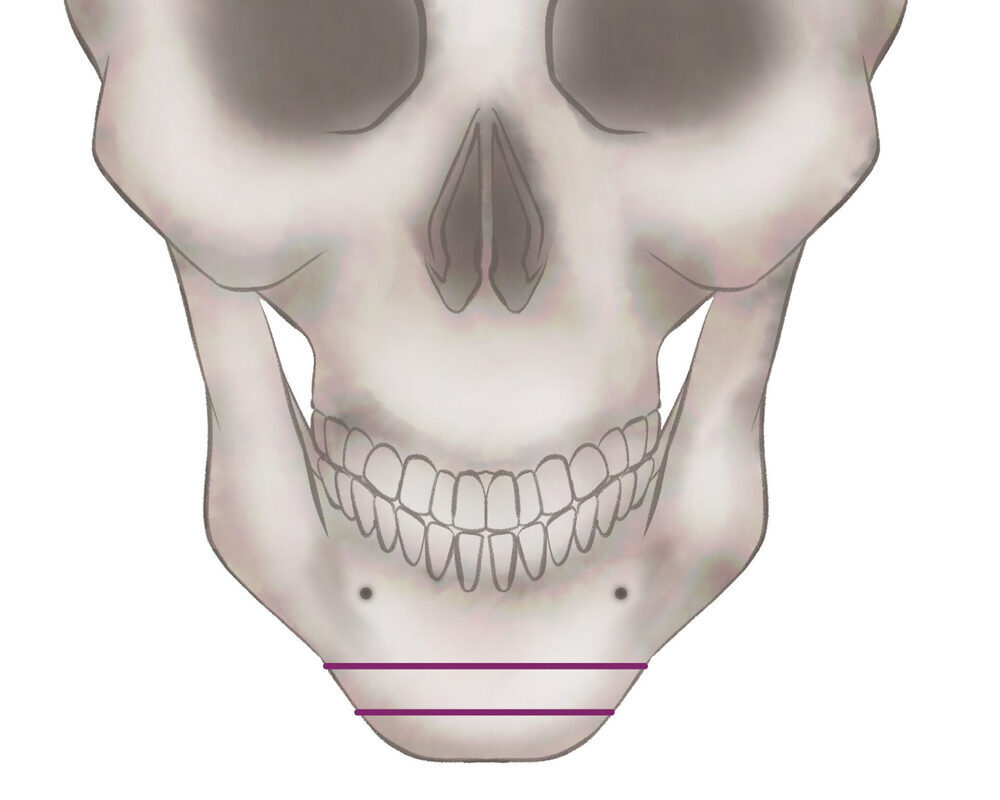

1.切開線をデザインします

2.骨を切除します

3.骨を移動させ段差を削ります

4.プレートで固定します